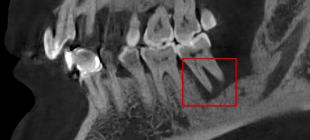

(2)阻生牙:可精确显示阻生牙的位置,与下牙槽神经管的关系,有无牙根弯曲,有无骨间隔,术前可预测术中损伤下牙槽神经的可能性。

口腔ct怎么拍摄【专科天地】没有口腔CT,你根本不会想到自己的牙齿长得多“奇葩”!_https://www.jmylbn.com_新闻资讯_第15张